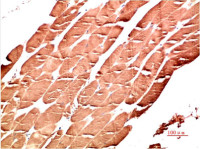

SARS-CoV-2 (COVID-19) nsp3 / PL-pro antibody [HL2350] detects SARS-CoV-2 (COVID-19) nsp3 / PL-pro protein by immunofluorescent analysis.

Sample: Mock and transfected 293T cells were fixed in 4% paraformaldehyde at RT for 15 min.

Green: SARS-CoV-2 (COVID-19) nsp3 / PL-pro stained by SARS-CoV-2 (COVID-19) nsp3 / PL-pro antibody [HL2350] (GTX638553) diluted at 1:500.

Blue: Fluoroshield with DAPI (GTX30920).